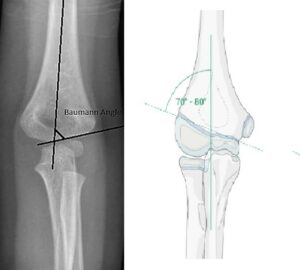

[toggle title=”Baumann açısı (Humerokapitellar açı)” state=”close”]

Lateral kondiler fizeal açı ile humerus uzun ark arasında kalan açıdır.

Normali 10-20°dir. Karşı eklemle karşılaştırılmalı, aralarındaki fark >5° olmamalıdır.

Distal humerus kırıklarının değerlendirilmesi yanı sıra kırıkta yapılan redüksiyon başarısının değerlendirilmesinde de kullanılır.